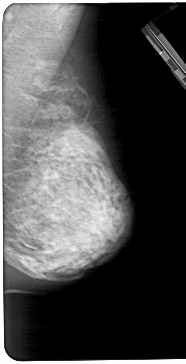

A_1282_1.LEFT_CC

LEFT_CC LINES 5266 PIXELS_PER_LINE 2761 BITS_PER_PIXEL 12 RESOLUTION 43.5 OVERLAY